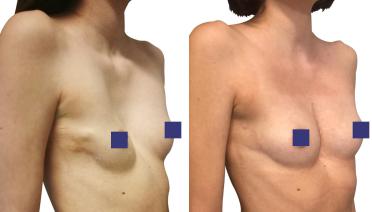

La tecnica di impianto su misura è una tecnica chirurgica minore che consiste nel riempire la concavità creata dal Pectus con un impianto personalizzato. Si tratta di un intervento rapido, a basso rischio, con un risultato immediato e una breve convalescenza.

In questa pagina, troverà i risultati di questa operazione a seconda del tipo di Pectus : mediale, asimmetrico, più o meno profondo o lungo.

Tipo 1 : Mediano, profondo e simmetrico,